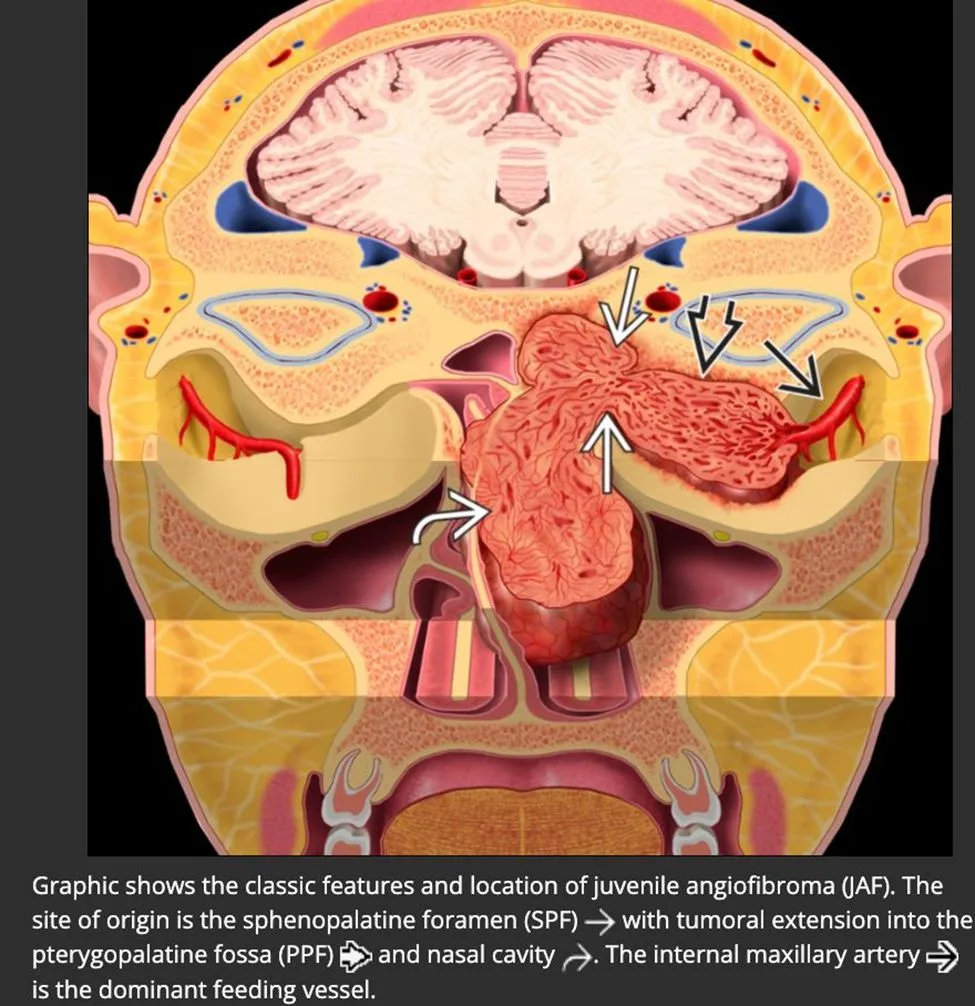

Juvenile nasopharyngeal angiofibroma commonly spreads from the sphenopalatine foramen into the {{c1::nasopharynx}} and {{c2::pterygopalatine fossa}} with associated bony remodeling

<b>Juvenile nasopharyngeal angiofibroma commonly </b>spreads from the sphenopalatine foramen into the {{c1::<u>nasopharynx</u>}} and {{c2::<u>pterygopalatine fossa</u>}} with associated bony remodeling